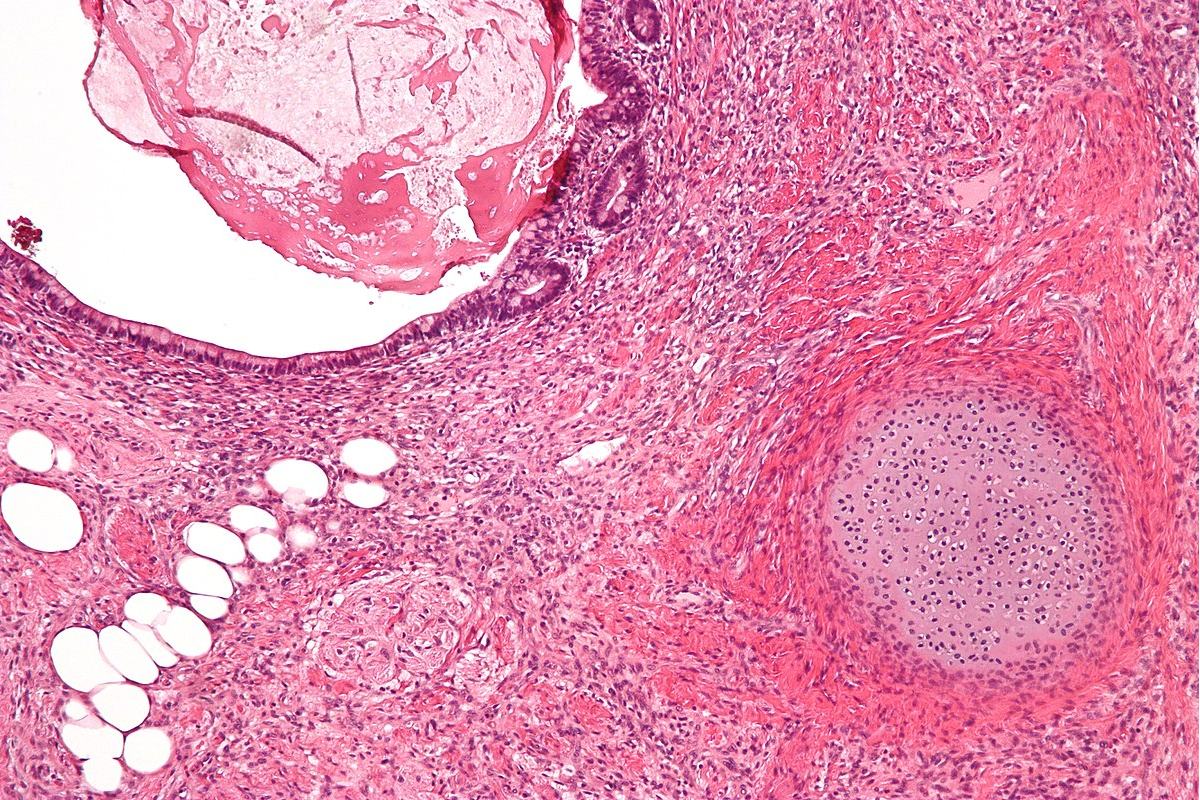

Qual a importância da certificação de qualidade na Patologia

A Certificação garante aos exames qualidade, rapidez e segurança para que os resultados possam auxiliar de forma positiva e clara no tratamento dos pacientes.